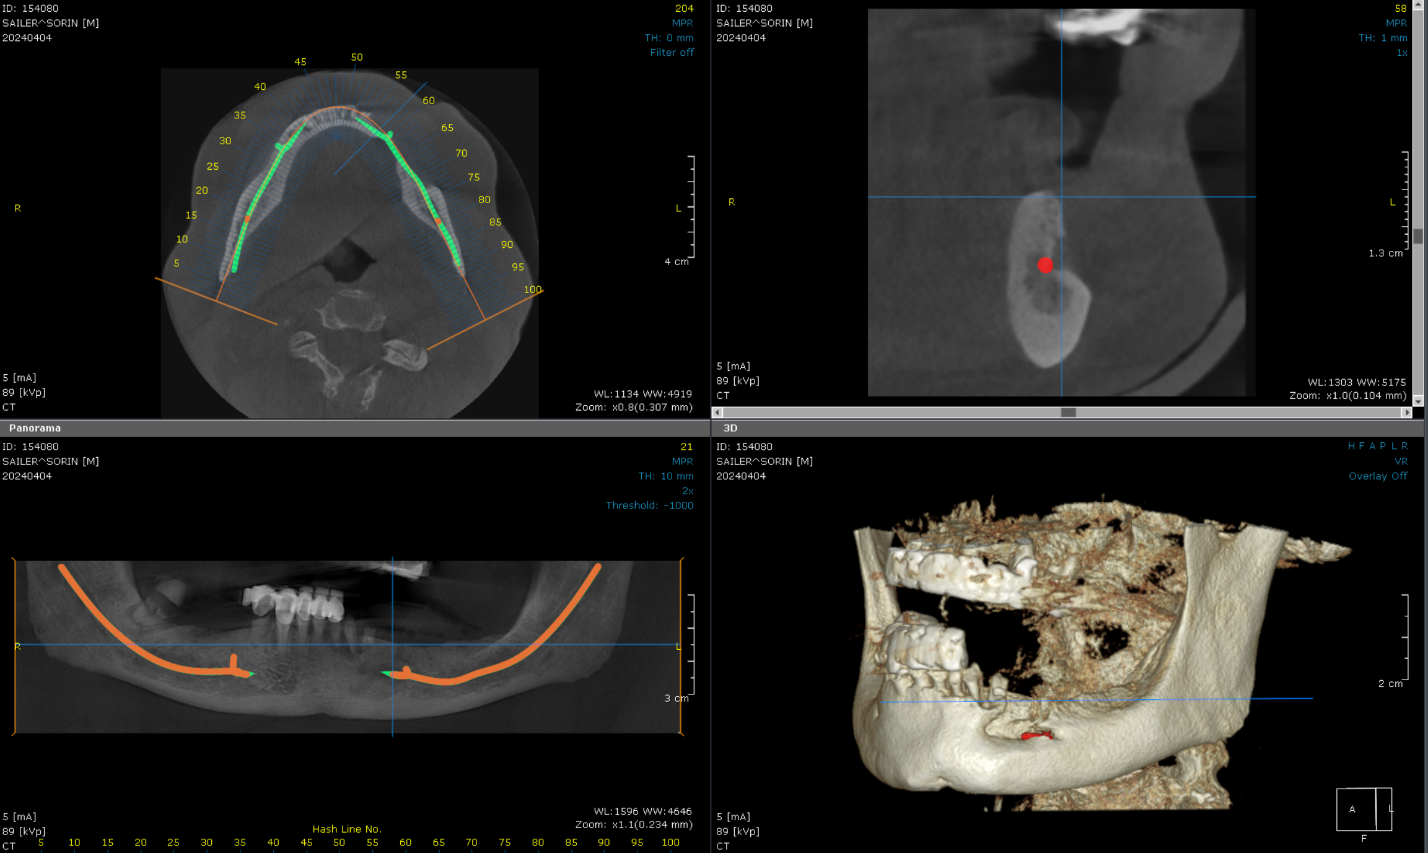

Cone Beam Computed Tomography (CBCT) scans were acquired for both the maxillary and mandibular arches. These scans provided critical insights into available bone volume, bone density, and anatomical considerations, forming a foundation for precise implant planning and guided surgery.

Patient had a new maxillary CT performed with the 2 dentures in occlusion.

Bone was measured to asses the amount of bone gained and the density of the said bone and also a first simulation of implant placement was performed.

Another view of the post graft healing in the mandibular arch and visibility of the composite marker additions done on the upper denture for alignment purposes between scan image and CBCT datasets.

Implant placement planning done in EXOPLAN involved careful digital matching of the CBCT, wax-up, and facial scan data, resulting in an accurate, digitally-produced try-in prosthesis (Fig. 8). The validated prosthetic design was subsequently integrated with the software to plan placement of five strategically positioned implants in the upper arch.